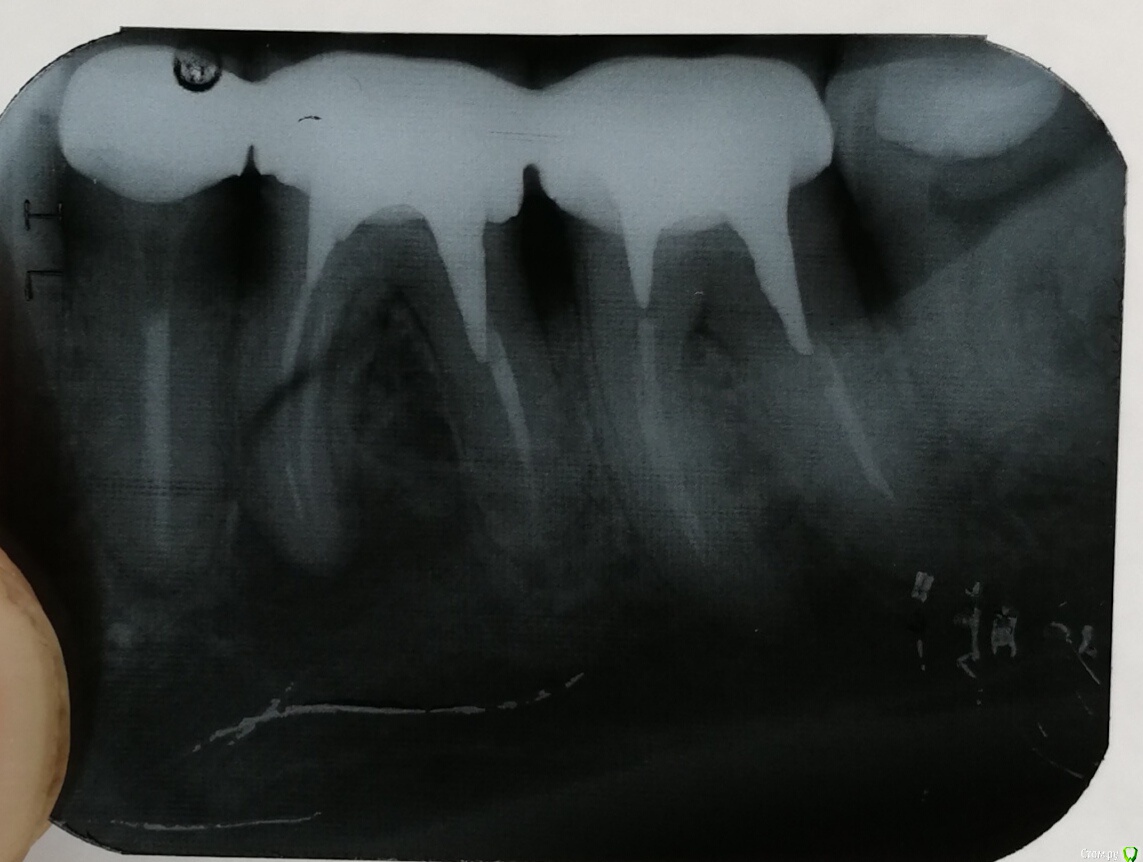

saintdim Опубликовано 4 сентября, 2018 Автор Поделиться Опубликовано 4 сентября, 2018 Качество снимка не позволяет его интерпретироватьсходил к другому врачу, у. Она сказала у меня перелом корня и поэтому болит. Ссылка на комментарий

red_butler Опубликовано 4 сентября, 2018 Поделиться Опубликовано 4 сентября, 2018 сходил к другому врачу, у. Она сказала у меня перелом корня и поэтому болит. не помогло... Нет у Вас перелома... 1 Ссылка на комментарий

сирена Опубликовано 4 сентября, 2018 Поделиться Опубликовано 4 сентября, 2018 Снимайте коронки и удаляйте шестой зуб.Перелечить его вряд ли получится.Попробовать можно,конечно,но это будет дорого.И без гарантии. Ссылка на комментарий

red_butler Опубликовано 5 сентября, 2018 Поделиться Опубликовано 5 сентября, 2018 Снимайте коронки и удаляйте шестой зуб.Перелечить его вряд ли получится.Попробовать можно,конечно,но это будет дорого.И без гарантии.Очно нужно смотреть Боль, если по баллам, то 10 из 10 это больше на пульпит похоже 8 зуб запломбированный, но с нервами Ссылка на комментарий